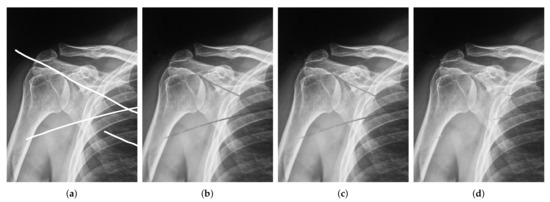

| Image Size | Image Size | |||

|---|---|---|---|---|

| SNR | SSIM | SNR | SSIM | |

| Algorithm 1 | 19.8276 | 0.9378 | 25.7210 | 0.9363 |

| Algorithm 2 | 20.4704 | 0.9402 | 26.2362 | 0.9373 |

| Algorithm 5 | 22.9158 | 0.9477 | 27.6581 | 0.9400 |